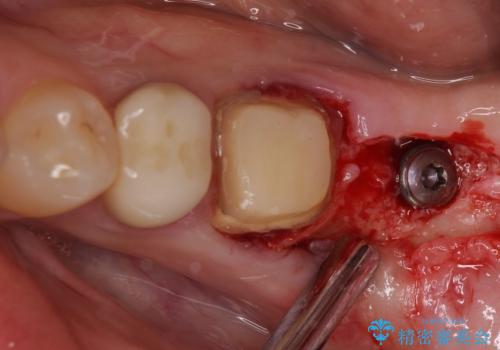

インプラント埋入にあたり、歯槽骨での炎症が広範囲であったことから、事前に骨造成を行いました。

歯槽骨の高さや幅を回復することができ、望ましい位置にインプラントを埋入することができました。